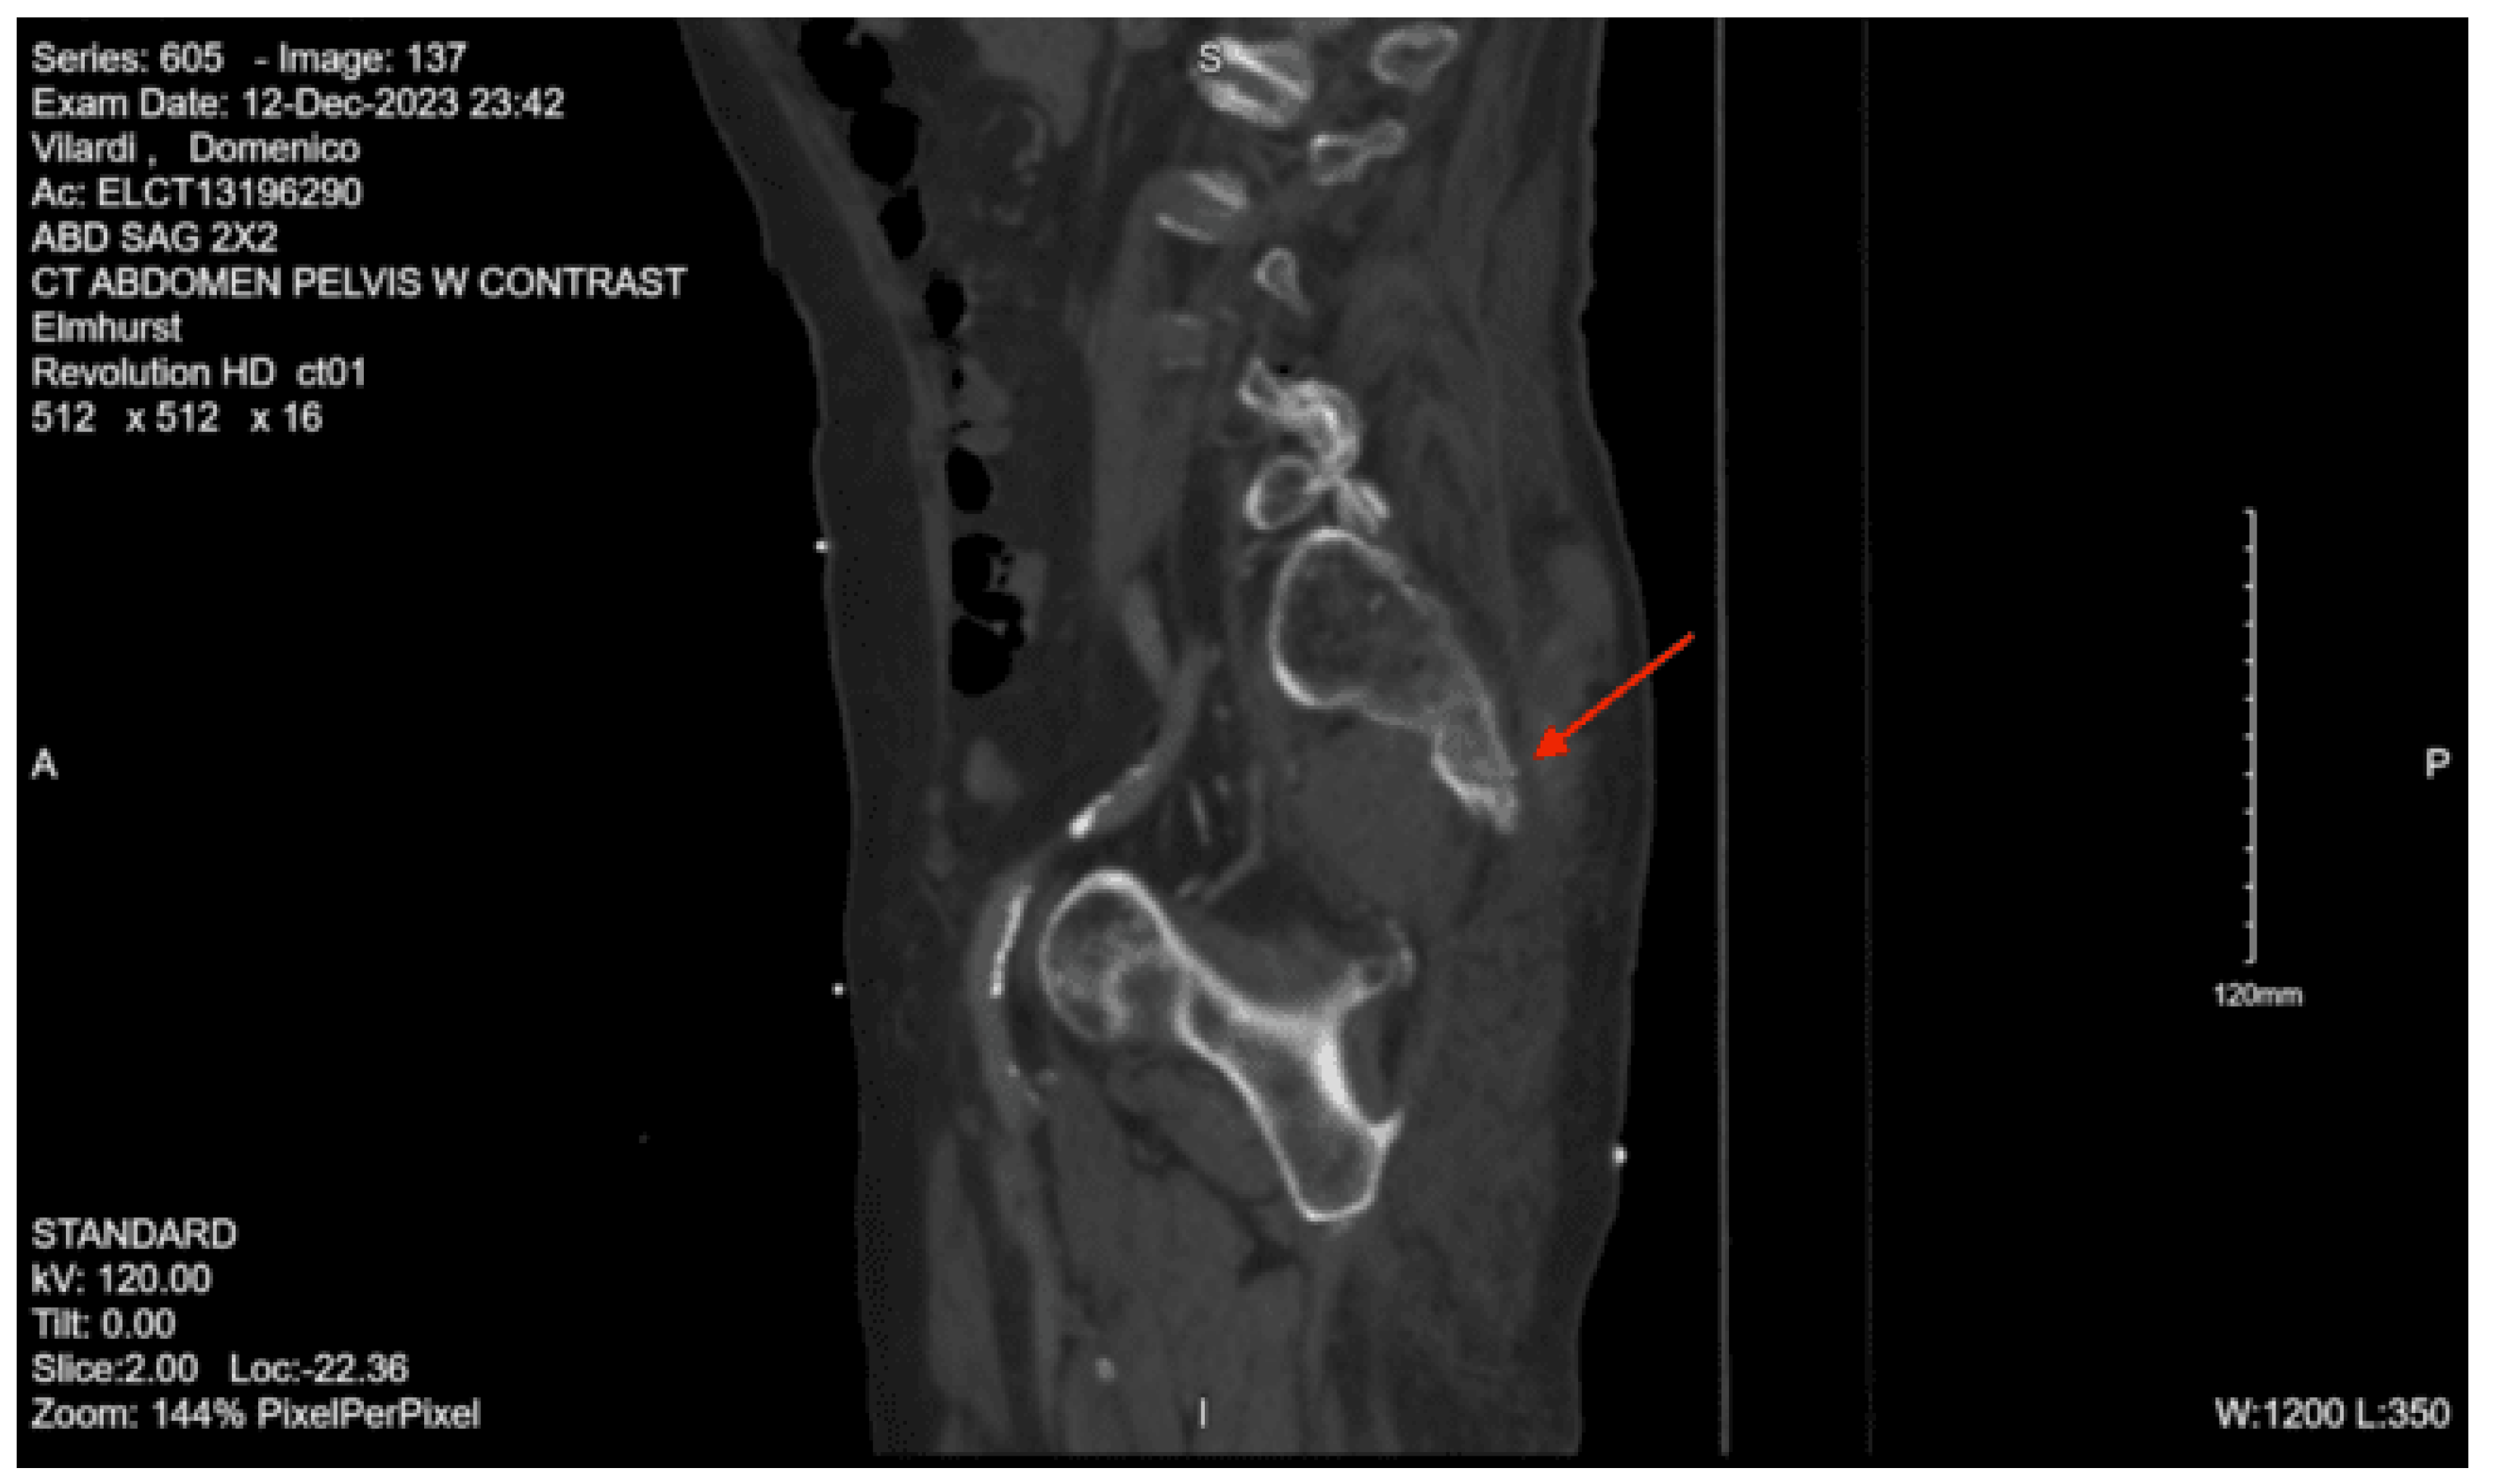

Imaging as shown in Figure 1, Figure 2 and Figure 3:

CT lumbar spine w/o contrast: An acute comminuted fracture is seen involving the superior portion of the left sacral wing. The SI joints are intact. Intact lumbar spine.

CT abdomen/pelvis with contrast: Acute fractures are seen involving the right superior pubic ramus and left inferior pubic ramus. An acute comminuted avulsed fracture of the left sacral wing in the superior and midportion is demonstrated. No definitive acute traumatic visceral abnormalities were found throughout the abdomen and pelvis.

DX: Denis zone II left sacral alar fx involving S1 foramina. AOSpine B3: NX, M3